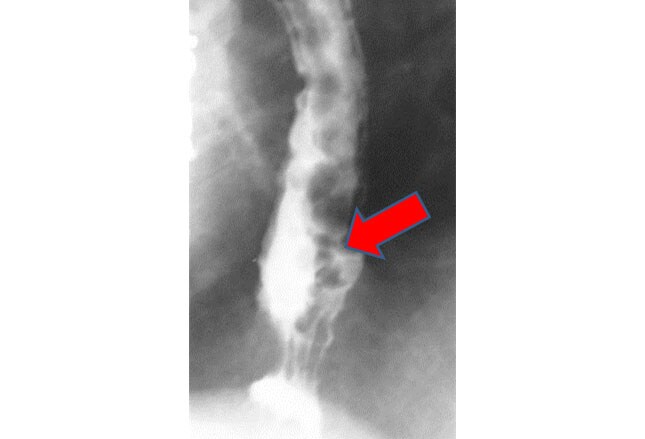

Staging Lung Cancer With Bone Metastases